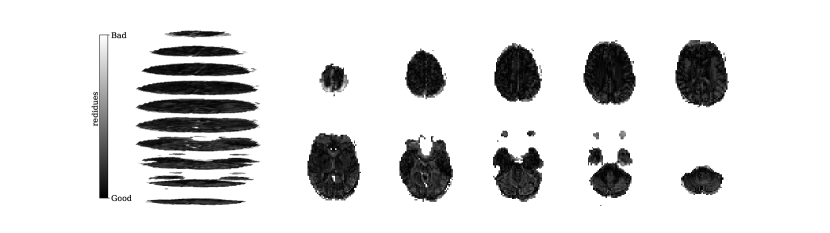

Figure 2 illustrates the distribution of residues (observed vs. estimated differences) on the fMRI volumes for the NODDI dataset. Clearly, by visual inspection, (iv) model has the darker and biggest area of shaded regions, which implies a better coverage across the brain regions and better synthesis quality. Models with topographical attention, (ii) and (iv), corresponding to Figures 2(b) and 2(d), respectively, significantly improve the synthesis, as shown by the darker and bigger areas against (i) and (iii) depicted in Figures 2(a) and 2(c), respectively. Particularly, we notice that models (i) and (iii) report difficulty in the retrieval of haemodynamical activity located in occipital and parietal lobes.

To better address which regions our baselines had more difficulty retrieving, the normalized residues were computed and are illustrated in Figure 3. Baselines – corresponding to models (i) and (ii), shown in Figures 3(a) and 3(b) respectively, which correspondingly implement a linear projection in the latent space and topographical attention –, have difficulty retrieving the prefrontal, occipital and parietal lobes, as the shade tends to a lighter grey in that region. Model (iv), shown in Figure 3(d), does not show a noticeable region with a lighter tone of grey, which implies no evident difficulty in retrieving haemodynamical activity across the different brain regions.